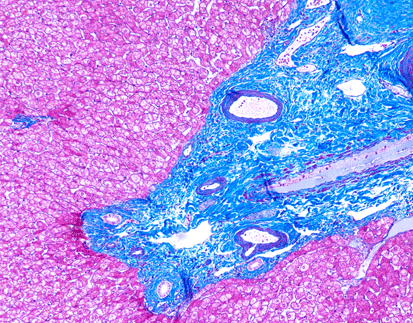

SPECIAL STAINS